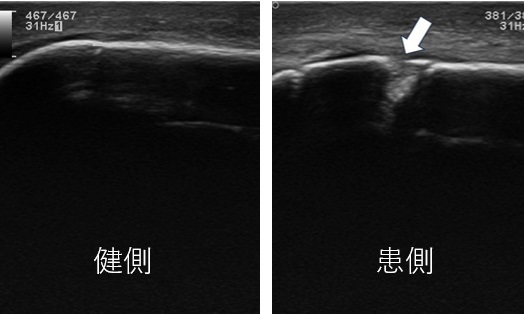

左:健側画像 右:患側画像

肘の後方に著明な腫脹を認め肘頭骨折が疑われた。

尺骨の肘頭部に不整像を認め骨折が観察される。